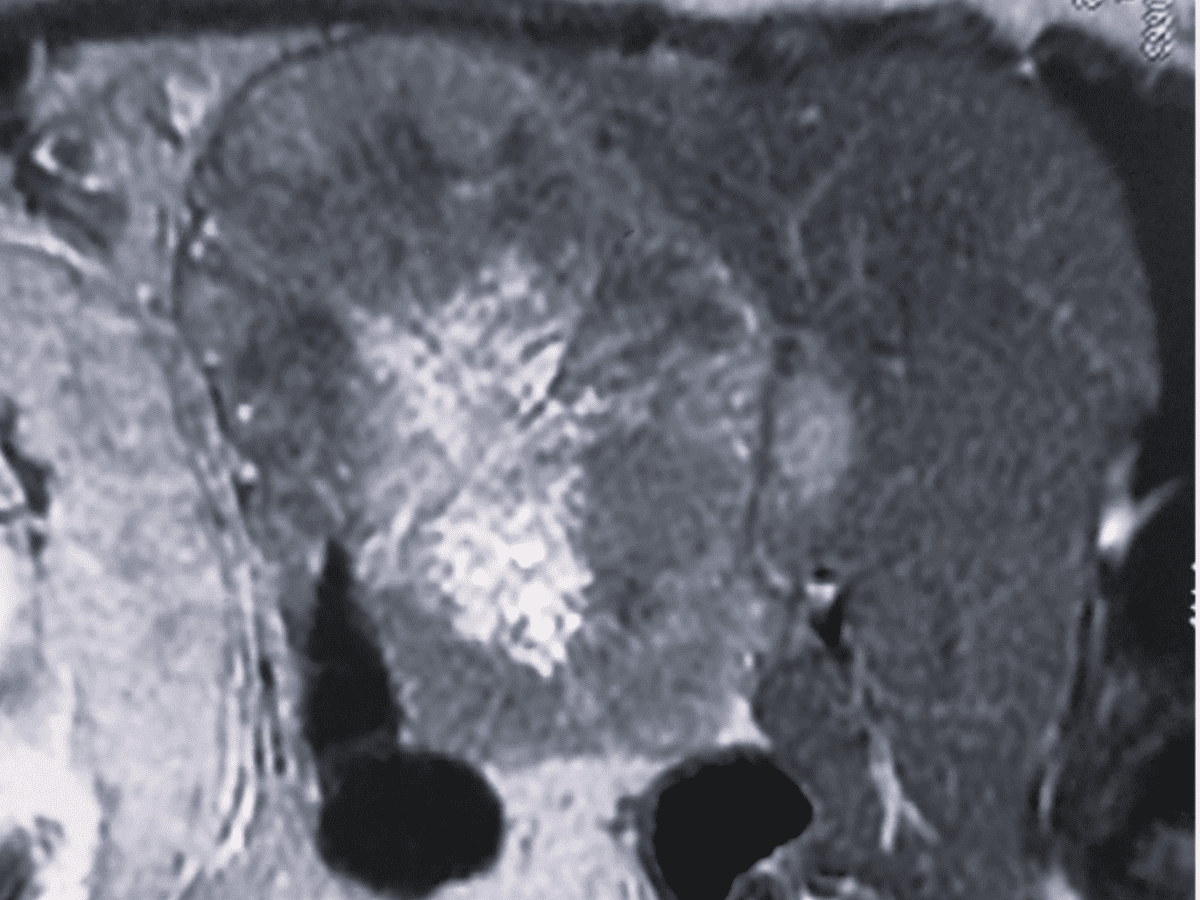

The 24-year-old woman, from Jangaon in Telangana, complained of a lump and ache in her stomach. Later the diagnosis revealed a cancerous tumour in her liver.

An interdisciplinary team for the operation was formed with doctors from the departments of surgical gastroenterology, gynaecology, and anesthesiology from NIMS and the Neonatology Department of Niloufer Hospital. The tumour was removed after a six-hour-long surgery and was found to be cancerous upon biopsy.